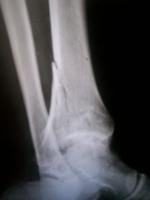

Definitivamente es una fractura difícil, no puedo ver bien en las imágenes que son muy pequeñas, pero parece verse un trazo articular. ¿O hay varios?

Gracias por la respuesta yo vivo en guerrero arcelia, caí de una altura de un metro poco menos, no dolió, no duele puedo mover dedos, y n siento ningún dolor calambre ya tengo dos meses de caído pero 15 días traía una férula, la verdad no hay muchos especialestas por acá, en chilpancingo uno digo operación, pero otro dijo yeso y pues, me pusieron hace casi 8 semanas bota de fibra de vidrio yo me siento bien no apoyo el pie sentado lo pongo en el piso y no me molesta pero la verdad, no se que tan mal esta o que pronostico tenga no puedo trabajar, pues es la pierna derecha y pues no se realmente para cuando me podre mover, manejar etc gracias

De verse bien, se ve.

Tal vez en un inicio yo habría optado por la cirugía, pero ahora se ve bastante bien.

¿Creoq eu el tiempo que llevas es buen tiempo y no de ven desplazados ls fragmentos

No veo mayor problema eh!

Creo que estas bien